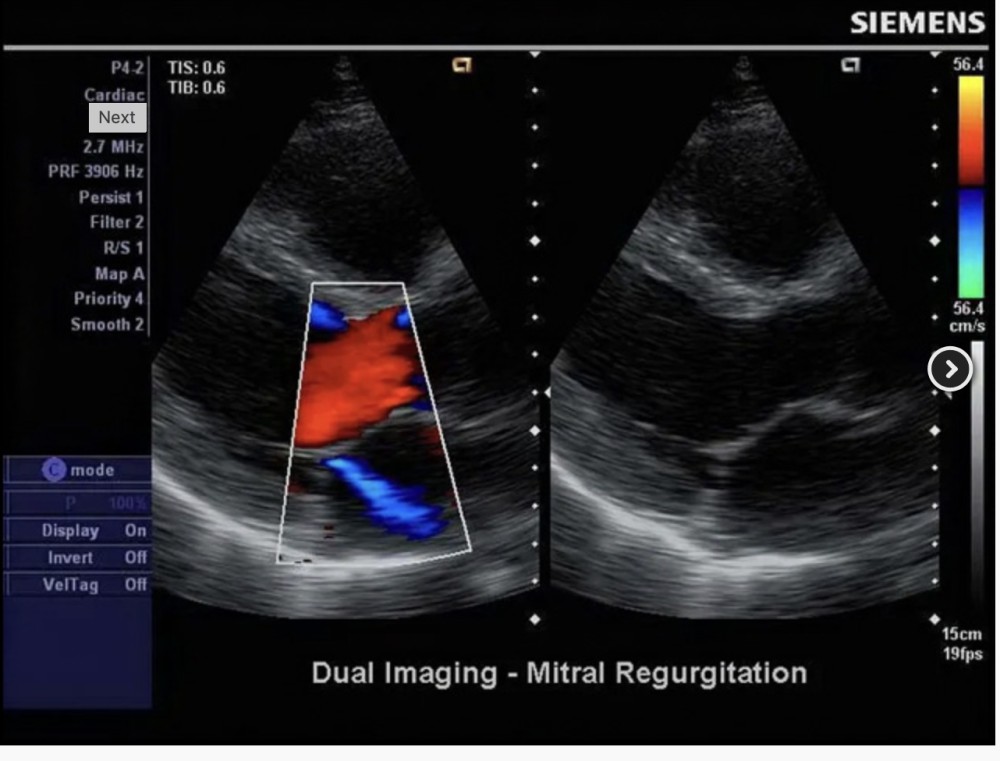

P4-2 Phased Array Probe

Tezlik: 1.3–4.4 MHz

Tətbiqlər: Abdominal, Böyük yaşlı ürək, Obstetriya

Elementlər: 64

Uyğunluq: X150, X300